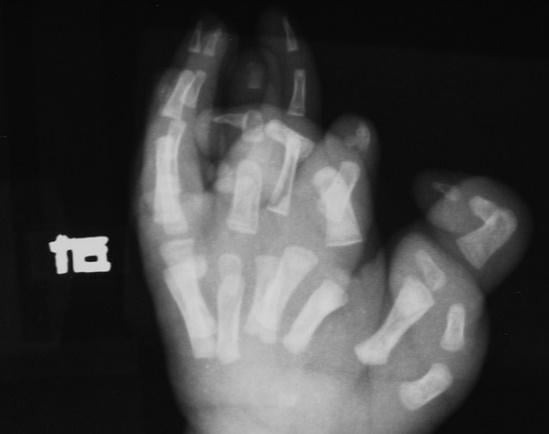

片手の指が11本もある男児の画像。

無事切除できた。